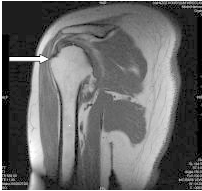

Którą strukturę anatomiczną oznaczono na obrazie rezonansu magnetycznego?

A. Trzon kości ramiennej.

B. Głowę kości ramiennej.

C. Guzek większy kości ramiennej.

D. Guzek mniejszy kości ramiennej.